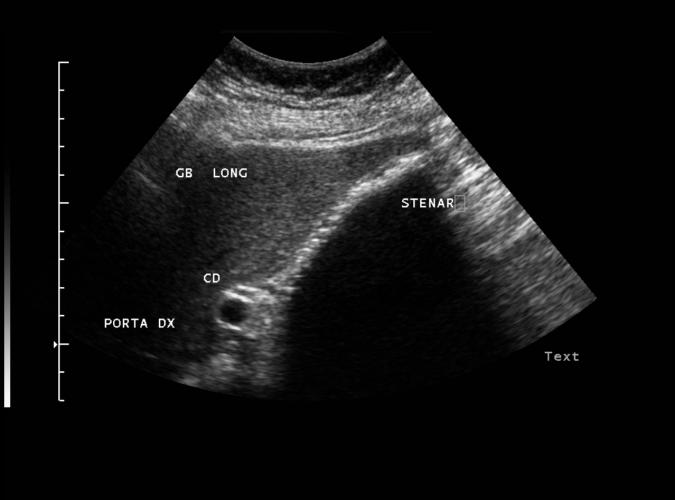

Long. Gallblåsa utfylld av stenar